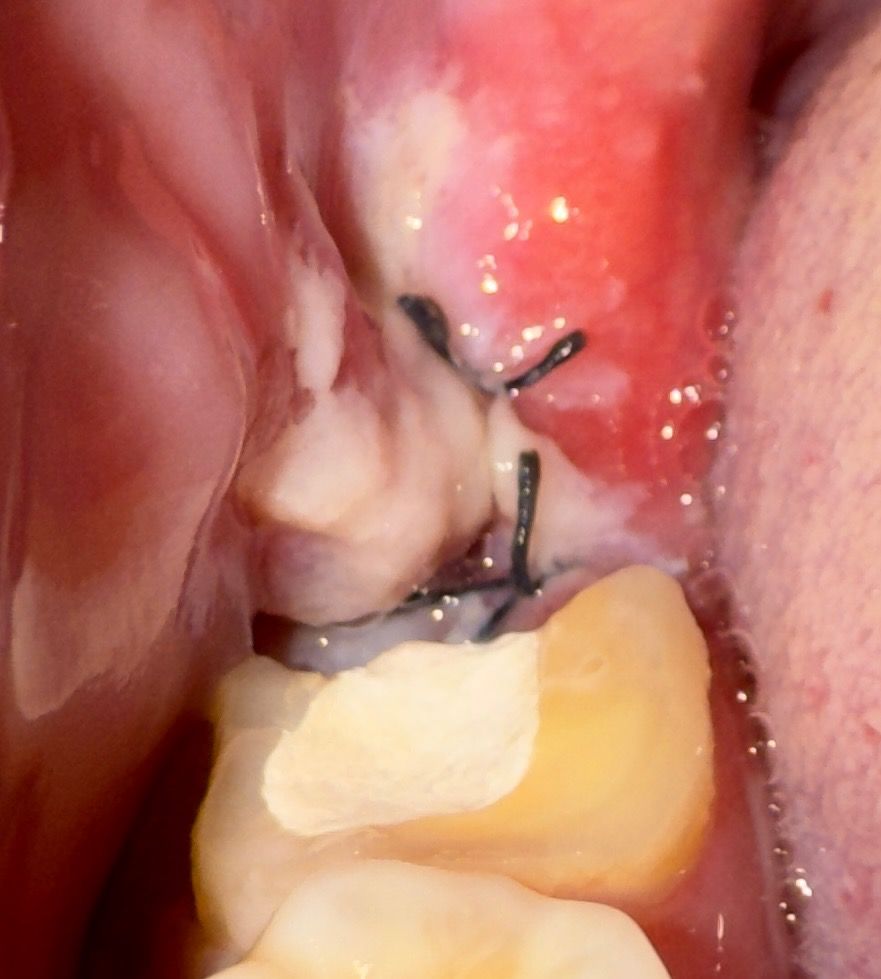

매복사랑니 발치 후 콜라겐 지혈제 사용

매복사랑니 발치 후 콜라겐지혈제 넣었는데..

저 하얀게 지혈제인가요? 염증인가요? 음식물인가요?

지혈제가 맞을 가능성이 높아보이며 자극을 주지 않으시는 것이 좋습니다. 잘 나을 것 같습니다.

하얗게 보이는게 지혈제 인거 같습니다 지혈제가 녹으면서 저렇게 보이는거니 건들지 마시고 그냥 두시면될것같습니다.

1. 지혈제를 넣고 봉합을 하기 때문에 저렇게 밖으로 보이진 않고요

2. 단순 이물질, 음식물로 보입니다

사진으로만 봤을 경우에는 하얀색 물질은 지혈제일 가능성이 높습니다. 발치를 하고 나면 발치한 부위가 자극이 되지 않도록 주의를 하는 것이 좋습니다.